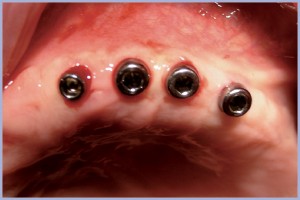

Si attendono 4 mesi controllando ogni 3 settimane il paziente per poi provvedere all’inconamento transitorio dei tappi di guarigione utilizzando dei mucotomi calibrati (Figg. 7, 8), e trascorse 3 settimane si esegue la simulazione e la scelta dei monconi con il kit dedicato di monconi di prova.

- Fig. 7

- Fig. 8